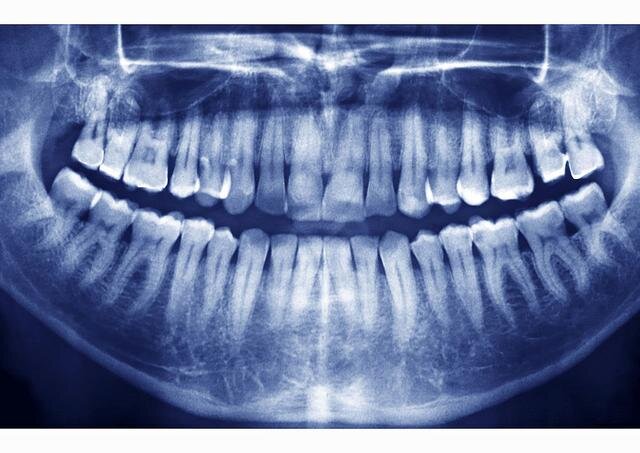

7-летнему мальчику удалено 526 зубов

Врачи удалили 526 зубов изо рта 7-летнего мальчика во время операции в Ченнаи, Индия. Мальчика доставили в больницу с опуханием челюсти. Врачи решили оперировать и обнаружили, что то, что они сказали, напоминало «массу, похожую на сумку», весом почти полфунта, в которой были зубы. «Это первый в мире случай, который был задокументирован, когда у одного человека было обнаружено так много мелких зубов», - заявили в стоматологическом колледже. В заявлении говорится, что это состояние известно как «сложный одонтом», и что удаление зубов потребовало пяти часов операции. Родители мальчика впервые привели его в больницу, когда ему было 3 года, после того как они заметили опухание в нижней правой челюсти. Но мальчик не сотрудничал с врачами, поэтому его состояние не диагностировалось, сообщил стоматологический колледж. «Это напоминало жемчуг в устрице», - сказал один из врачей, согласно заявлению.